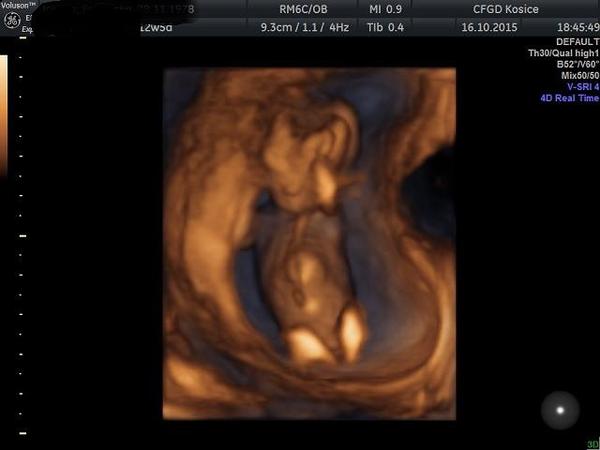

Dnes som bola na kontrole.Vraj to je akrobatka,nožičky mala vystreté,chodidlá za hlavou.ale v tomto období často menia polohu,všelijako,majú ešte dosť miesta.